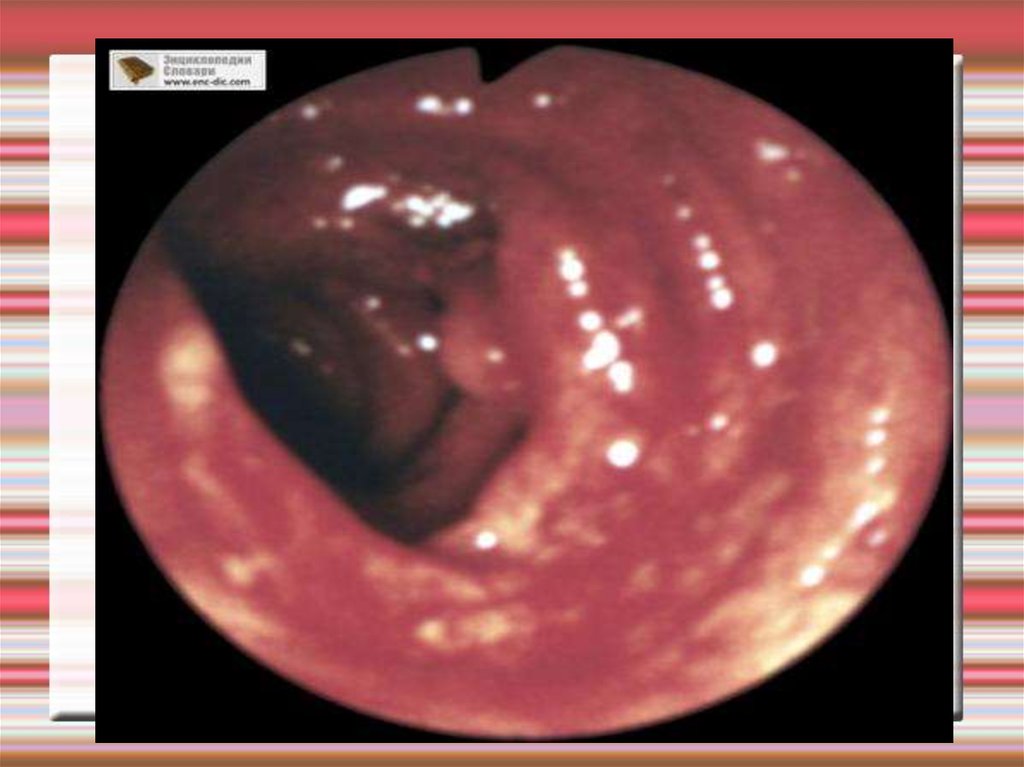

Болезнь Крона

Характеризуется сегментарным трансмуральным поражением толстой кишки с

распространением воспаления на все слои кишечной

стенки.

39. Болезнь Крона